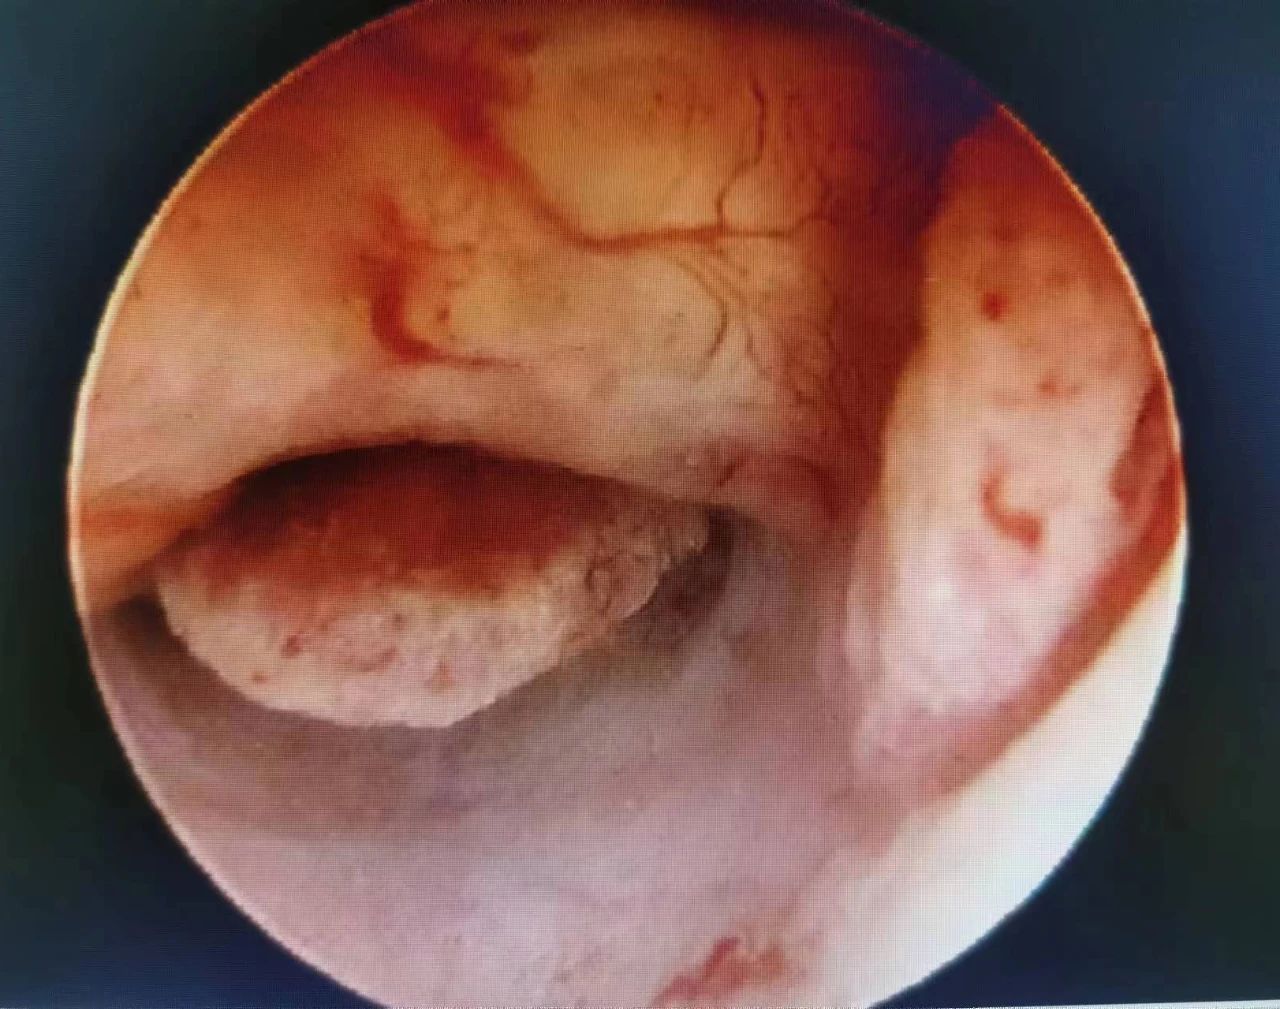

宫腔镜下可见子宫内膜息肉样增生